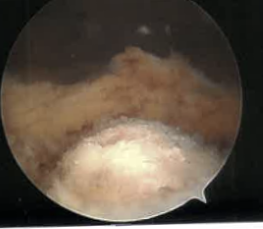

Intra-articular Osteoid osteoma

Issue

Risk cartilage damage from RF ablation

Options

Arthroscopic resection

Results

Ge et al Eur J Orthop Surg Traumatol 2020

- systematic review of arthroscopic treatment of upper limb osteoid osteomas

- 32 cases in 19 articles involving shoulder / elbow / wrist

- no recurrence

- success rate 94%

- 2/24 (8%) in the elbow had incomplete resection